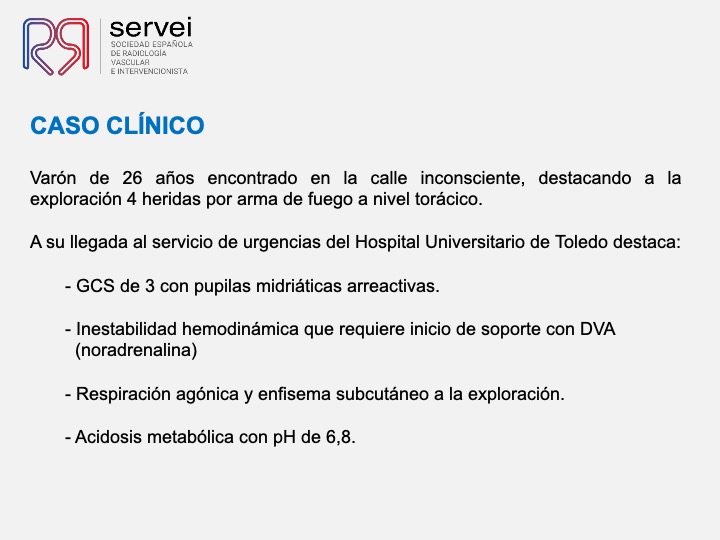

- Pseudoaneurisma pulnonar herida arma fuego 02